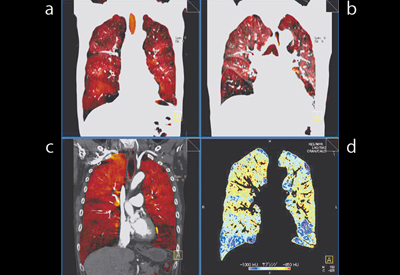

コロナル画像(図5)では, Xeの取り込みが少なく,parenchyma画像で青く表示される上肺野・下肺野の肺気腫の部位について,Lung PBVでも血流の低下が認められ,肺気腫・LAA・血流低下が相関していることがわかる。

図5 症例1:肺気腫,GOLDU(コロナル画像)

a:Xeイメージ(吸気) b:Xeイメージ(呼気)

c:Lung PBV d:parenchyma画像(呼気LAA)

図8に,症例2のコロナル画像を示す。

![]() 図7 症例2:CPFE(72歳,男性),下肺野,アキシャル画像 a:Xeイメージ b:parenchyma画像 c:Lung PBV d:単純CT画像 |

![]() 図8 症例2:CPFE(72歳,男性),コロナル画像 a:Xeイメージ(吸気) b:Xeイメージ(呼気) c:Lung PBV d:parenchyma画像 |